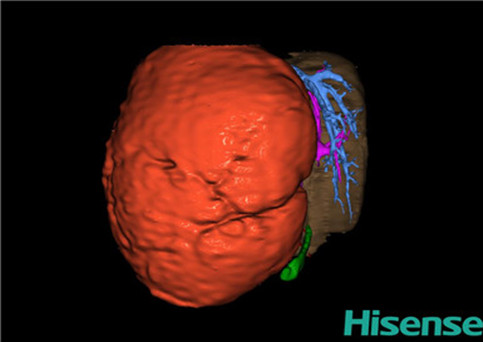

目前常用的检查方法有B超检查、CT、MRI、血管造影等。与其它的腹部肿块的诊断不同,对于小儿肝母细胞瘤血管造影具有重要的意义,可以作为手术前介入治疗的手段,也可为手术提供非常有效的影像学指导,但技术要求高,操作较复杂,且给患儿带来一定的痛苦。近年借助计算机辅助手术系统进行CT原始影像三维重建、手术规划和计算机虚拟手术技术,为精准肝脏手术提供了极为有效的技术支持。

近年来由于数字医学的发展,基于可视化三维重建技术的计算机辅助手术系统极大推进了小儿肝脏肿瘤的精准手术的进步。可以立体透视肝脏解剖、精确掌握肝段的边界、精确测算肝段乃至任意血管所支配的功能体积、准确定位病灶及其与邻近血管的解剖关系,最终对不同手术方案进行比较、筛选和优化。因此,计算机辅助手术规划系统是实现精准肝切除的有力辅助工具,是未来数字外科、精准外科等21世纪外科新理念的重要技术支撑。

计算机辅助手术规划系统具有良好的操作可行性、计算准确性和三维显示效果,可半透明、交互式显示真实的肝内立体解剖关系和空间管道变异,准确计算肝内管道的直径、走行角度,两点间的垂直距离,和任意血管的支配或引流范围等传统二维影像无法获取的信息,有助于实施个体化手术,提高了手术的确定性、预见性和可控性。计算机辅助手术规划系统可直观显示预留肝脏的结构和功能,并可通过虚拟切割功能辅助术者对手术方案进行蹄选和优化,系统评估手术风险和制定对策,改变了部分二维规划的术式和切除范围,使部分二维规划认为不能切除的患者成功手术,提高了手术的根治性、安全性和病变的可切除性,更加符合精准肝脏外科的术前规划要求。详见第11章。

随着计算机技术及影像检查技术的不断发展,以精确的术前影像学和功能评估、精细的手术操作为核心的精准肝切除技术日益受到重视。基于数字医学的计算机辅助手术技术(computer-assisted surgery,CAS)则是实现肝脏精准手术操作的基础。计算机辅助手术系统(CAS)可将术前二维(two dimensional,2D)的CT/MRI影像数据进行三维(three dimensional,3D)重建,建立个体化的肝脏三维解剖模型,清晰显示肝脏内脉管系统的走行及解剖关系,还原病灶与其周围脉管结构的立体解剖构象,准确地对病变进行定位、定性和评估,制定合理、定量的手术方案,实施个体化的肝脏血管取舍分配方案及实施精准肝脏手术。一般认为CAS包括:创建虚拟的患者的图像;患者图像的分析与深度处理;诊断、手术前规划、手术步骤的模拟;术中实时导航。应用本技术后,由于可以更清晰地看出肿瘤的界限,特别是根据肝血管的显影,判断出肿瘤与门静脉及肝静脉的关系以在手术前较准确地估计出手术成功切除的可行性。以往部分根据普通强化CT判断无法手术的病例而被评估为可以成功切除并手术成功。